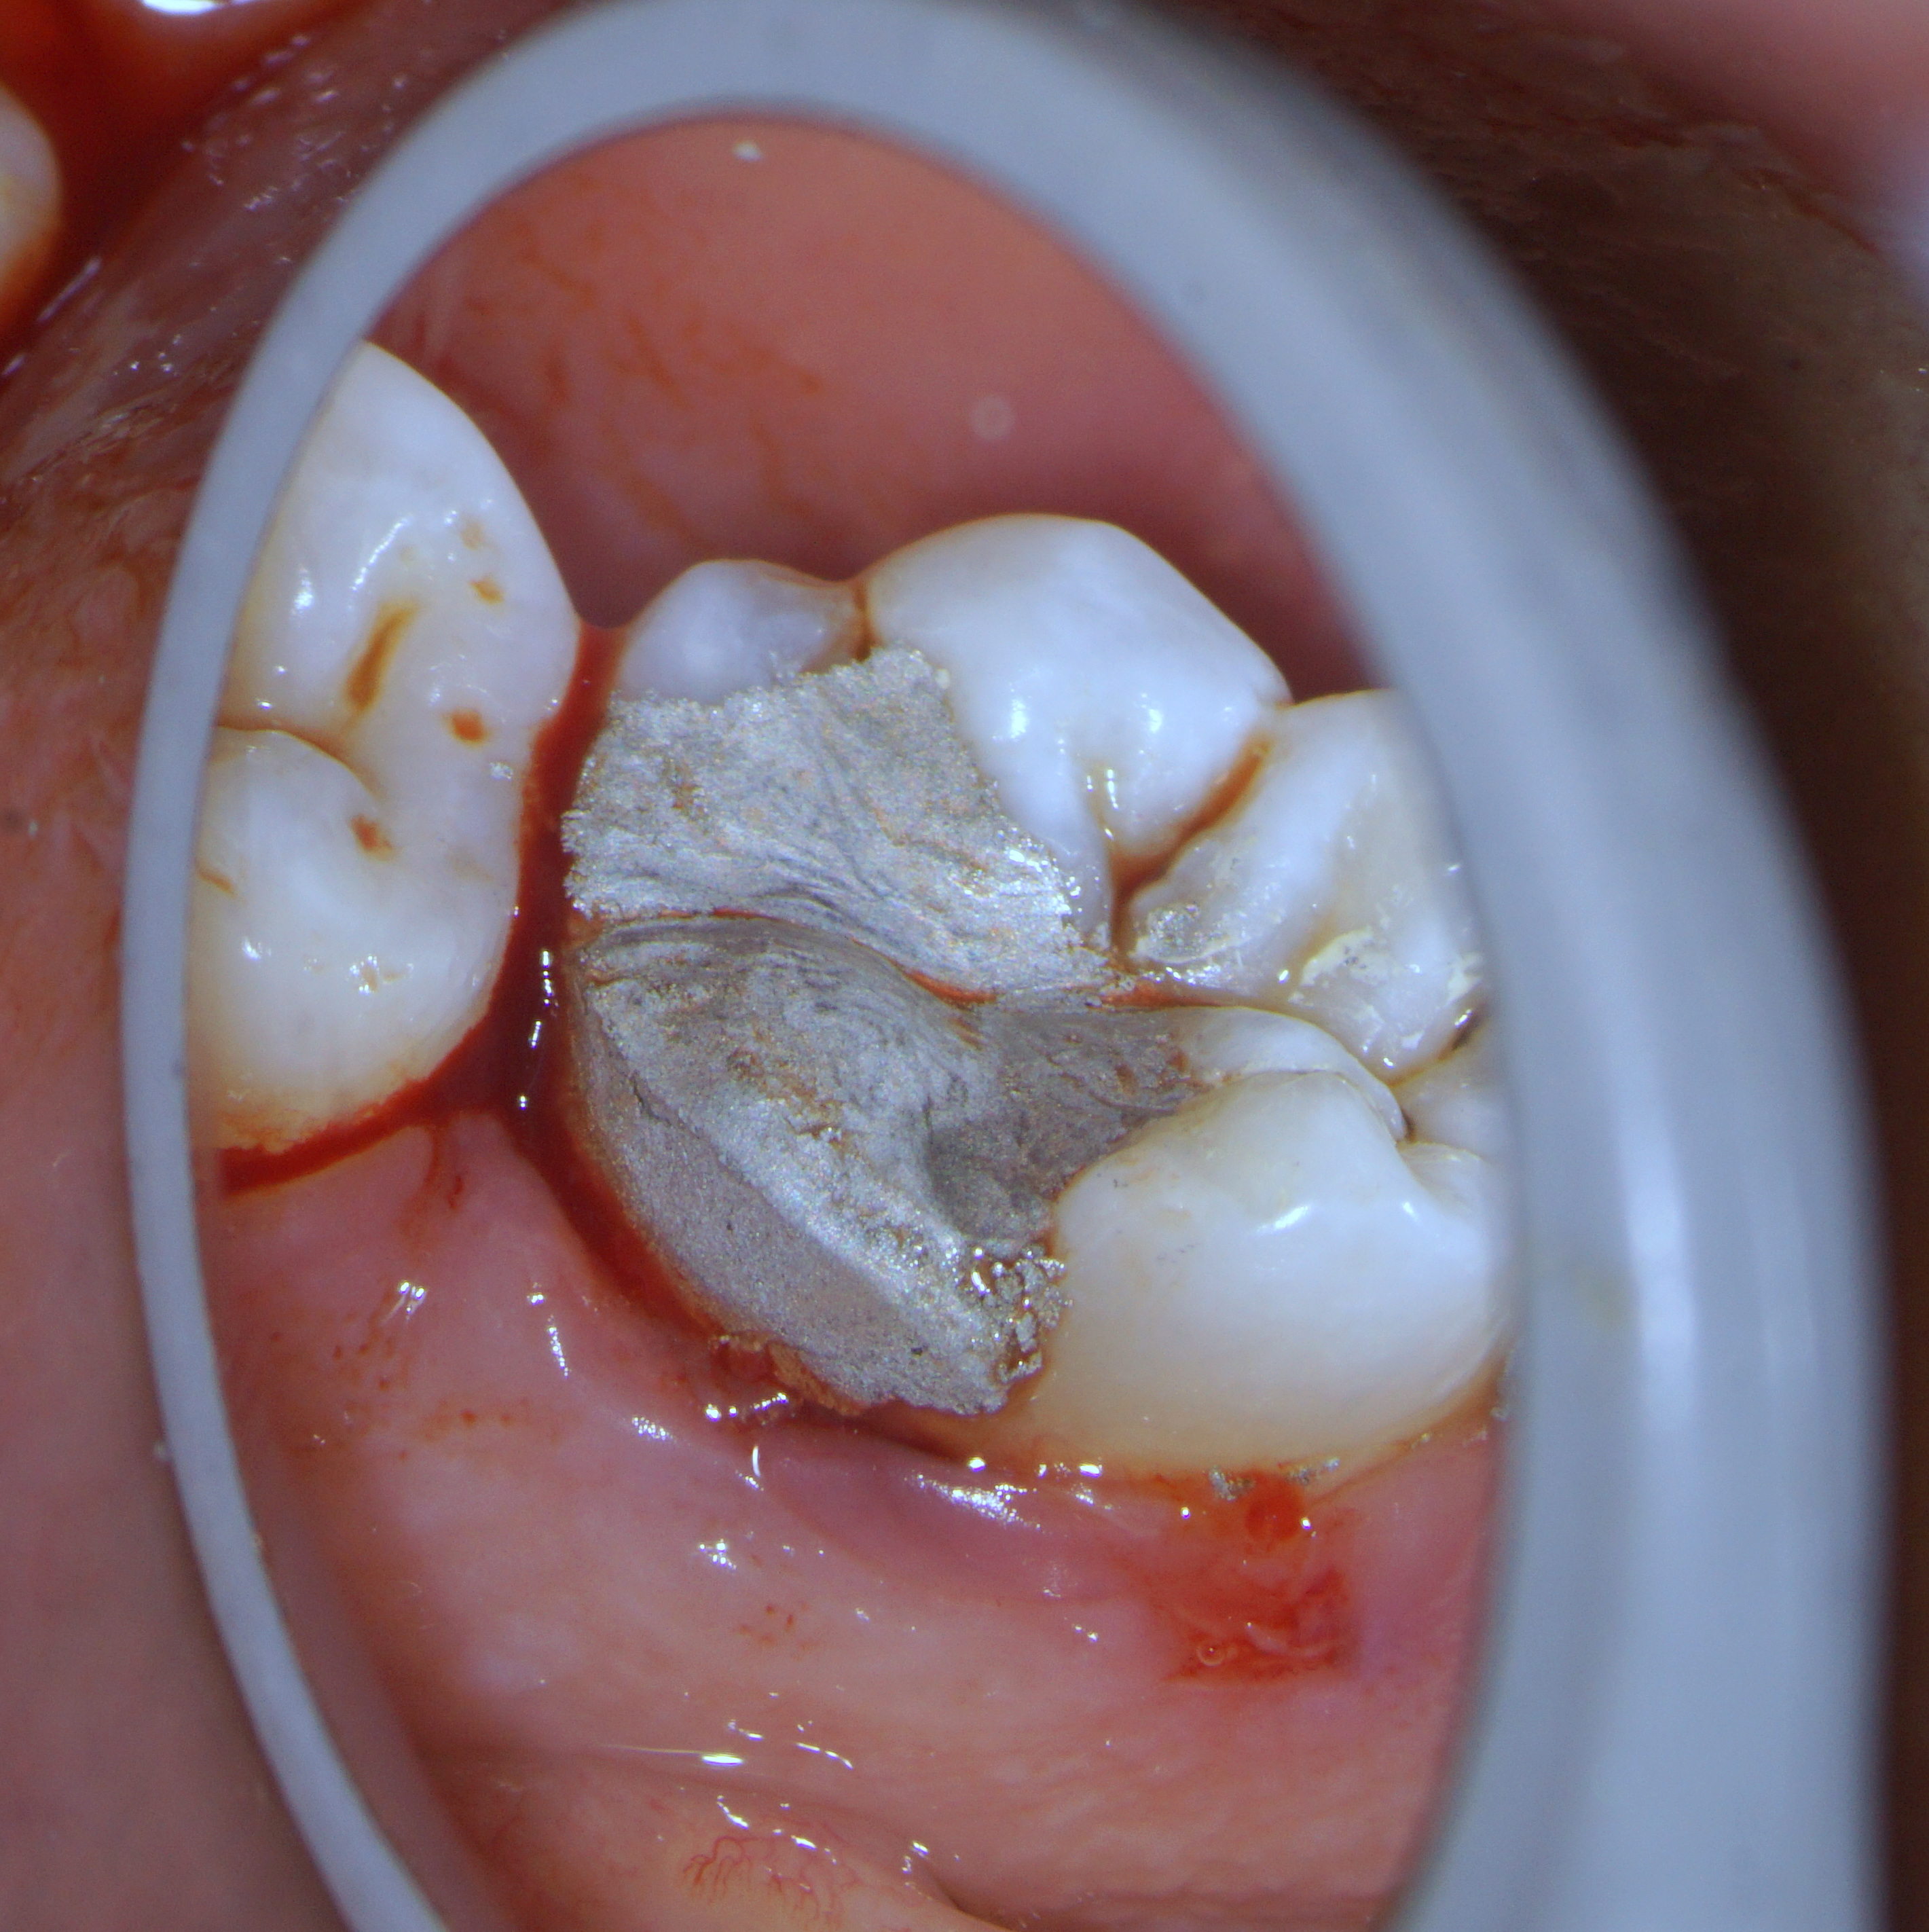

46 – Caries driven access

#46 with caries involving the DL cusp. The amount of tooth structure that would be lost if a conventional SLA access is opted for unimaginable. But i did have SLA in this case as well but from the back 😉